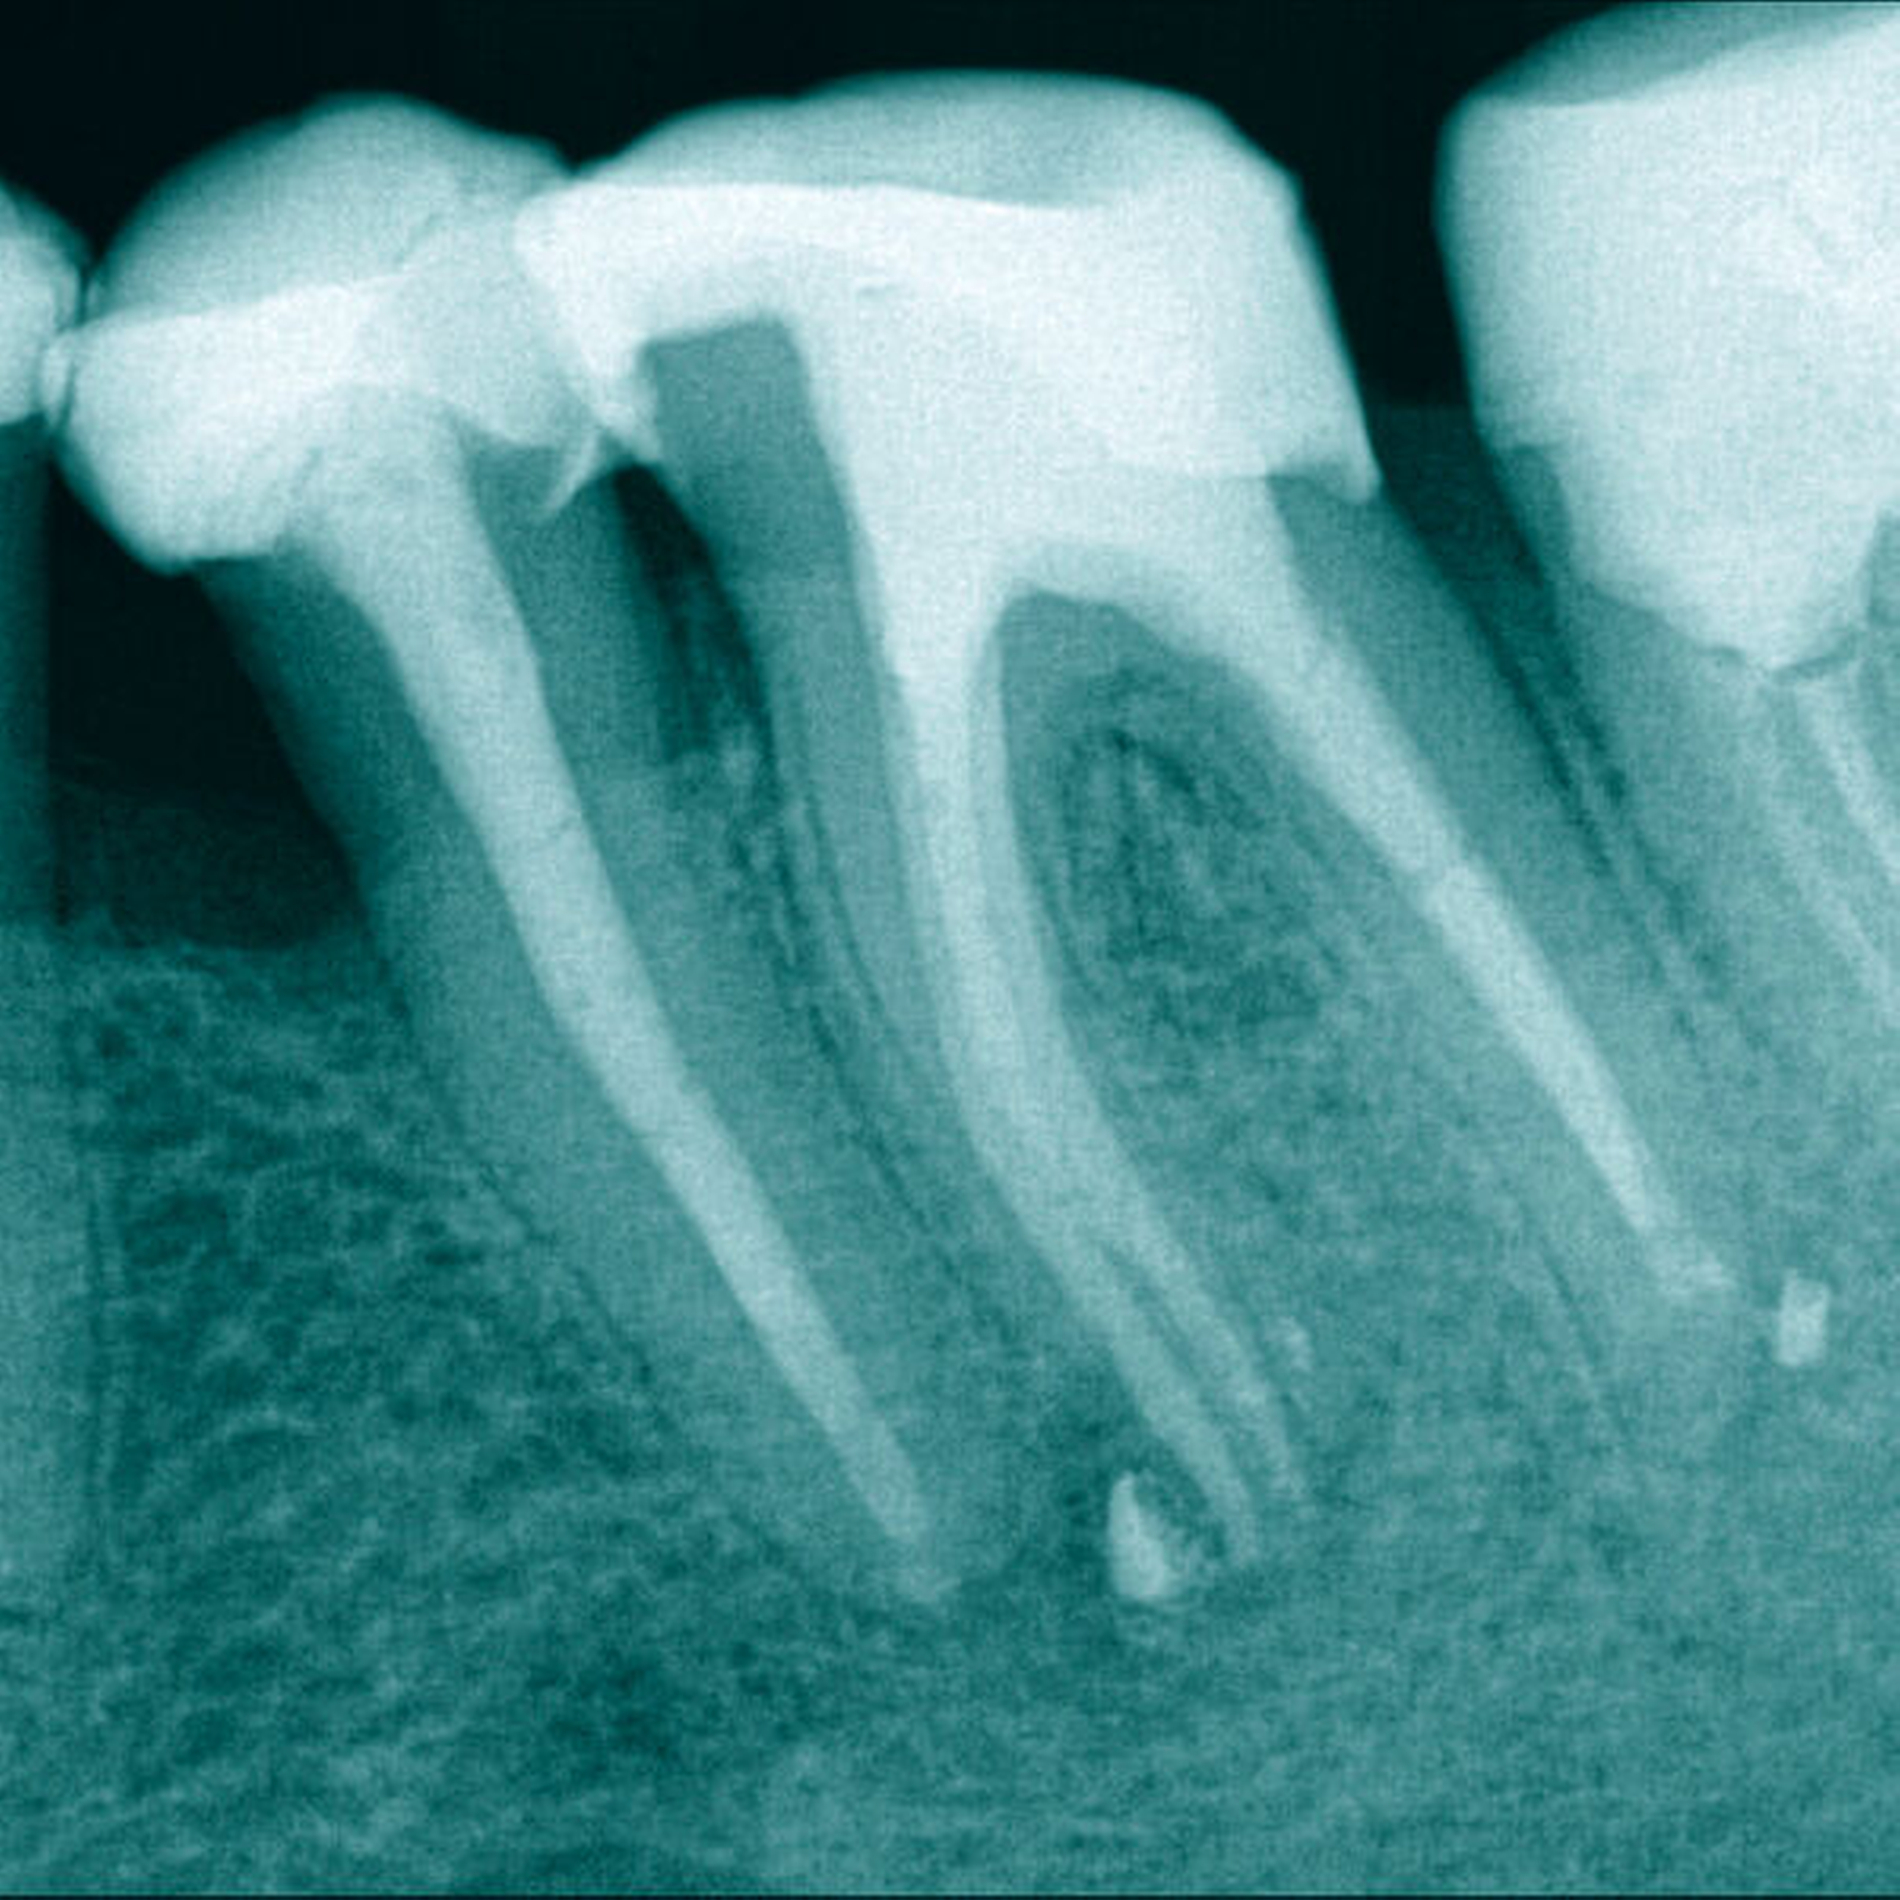

Eine 37-jährige Patientin mit einem frakturierten Nickel-Titan-Instrument in der mesiolingualen Wurzel von Zahn 36 wurde zur Weiterbehandlung überwiesen (Abbildung 6).

Mit einer Reciproc R25 (VDW) wurde zuerst die koronale Wurzelfüllung (Abbildung 7) entfernt, anschließend wurden die Kanaleingänge erweitert. Wie bei Fall 1 wurde zunächst das Fragment circa 3 mm koronal mittels Ultraschalltechnik (VDW Ultra/Endo Chuck) freigelegt und mit der oben beschriebenen Technik entfernt (Abbildung 8).

Auch in diesem Fall konnte in allen drei Wurzelkanälen Durchgängigkeit erreicht werden. Die chemomechanische Aufbereitung und Obturation (warm-vertikal modifiziert nach Schilder) der Wurzelkanäle erfolgte in zwei weiteren Sitzungen (Abbildung 9). Nach acht Monaten erfolgte der erste Recall, wobei eine deutliche Heilungstendenz erkennbar war (Abbildung 10).